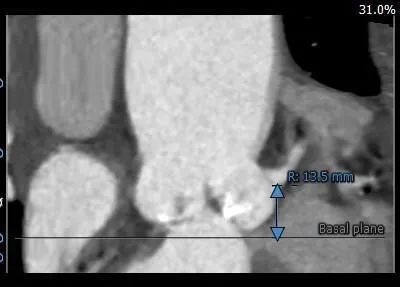

主动脉根部测量:

冠脉测量: